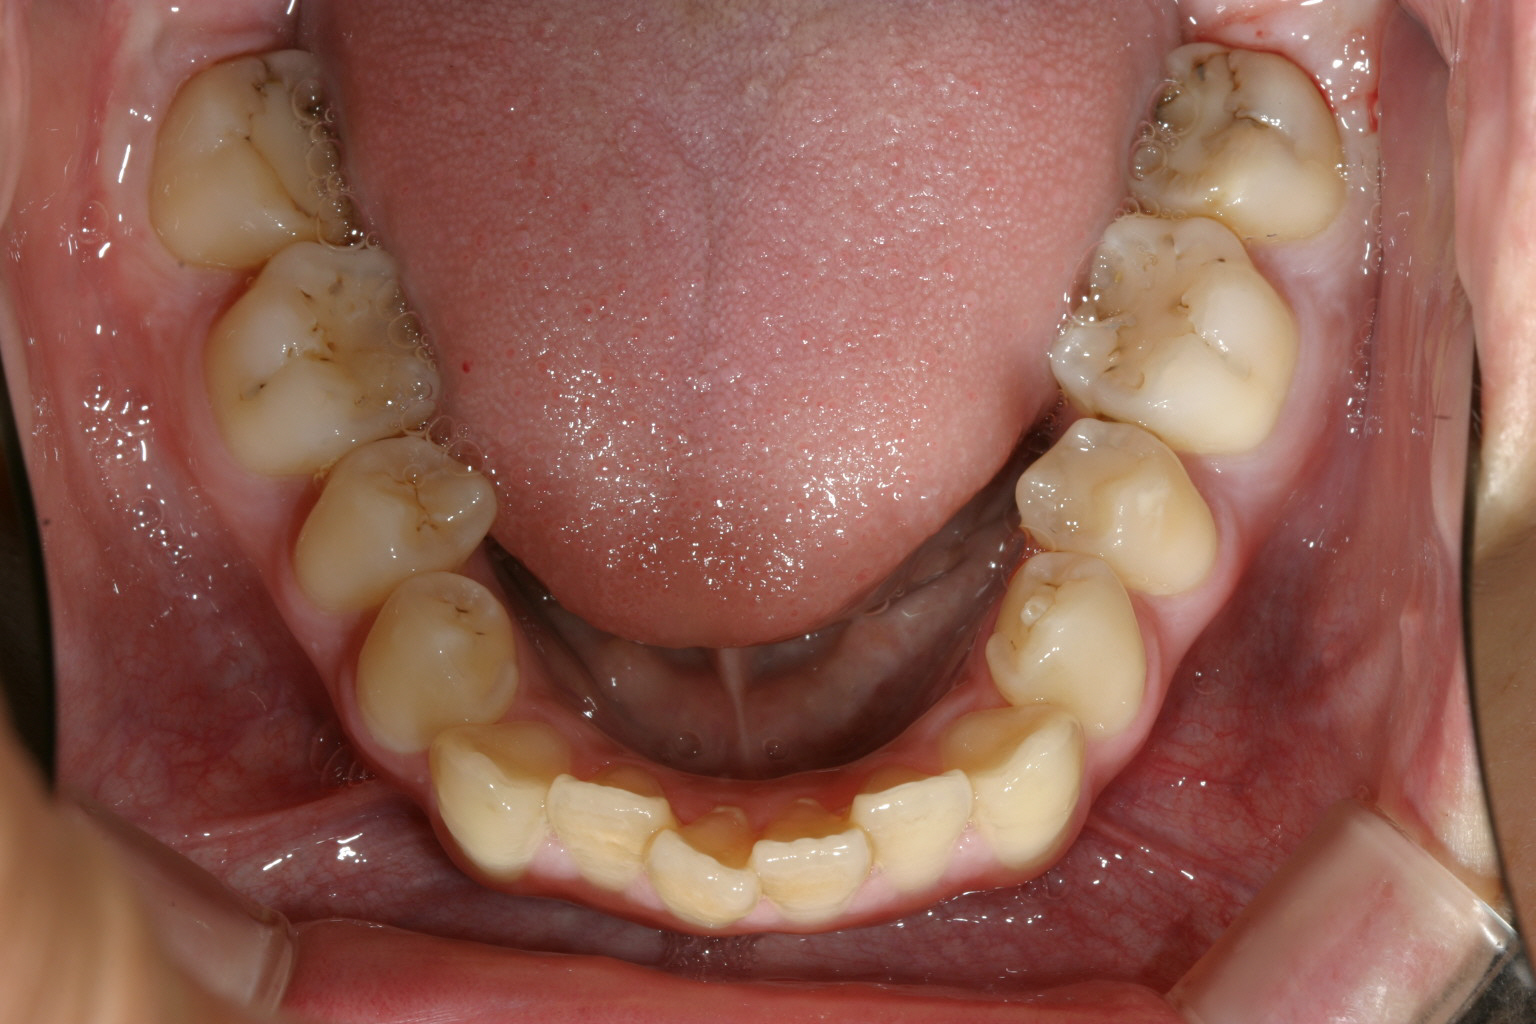

下顎もアーチが狭い為に前歯にガタつきが見受けられます。

下顎は非抜歯です。アーチをU字に変えて綺麗に並んでます。